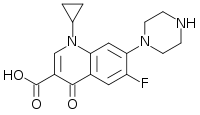

| Various pharmaceutical tuberculosis treatments and their actions | |

Ciprofloxacin |

CIP | (none) |

- fluoroquinolones (WHO group 3): e.g., ciprofloxacin (CIP), levofloxacin, moxifloxacin (MXF);